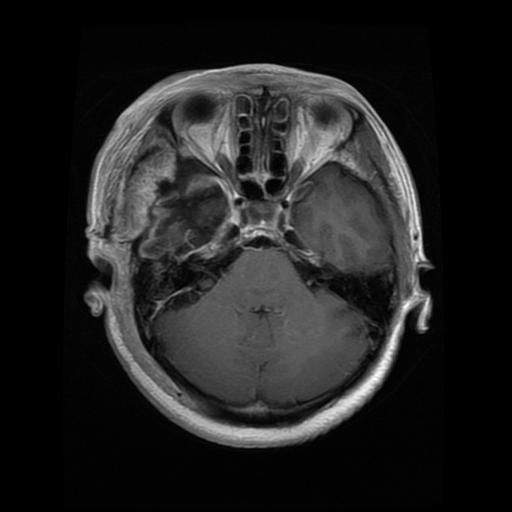

Meningioma

Meningioma

Meningioma

Meningioma